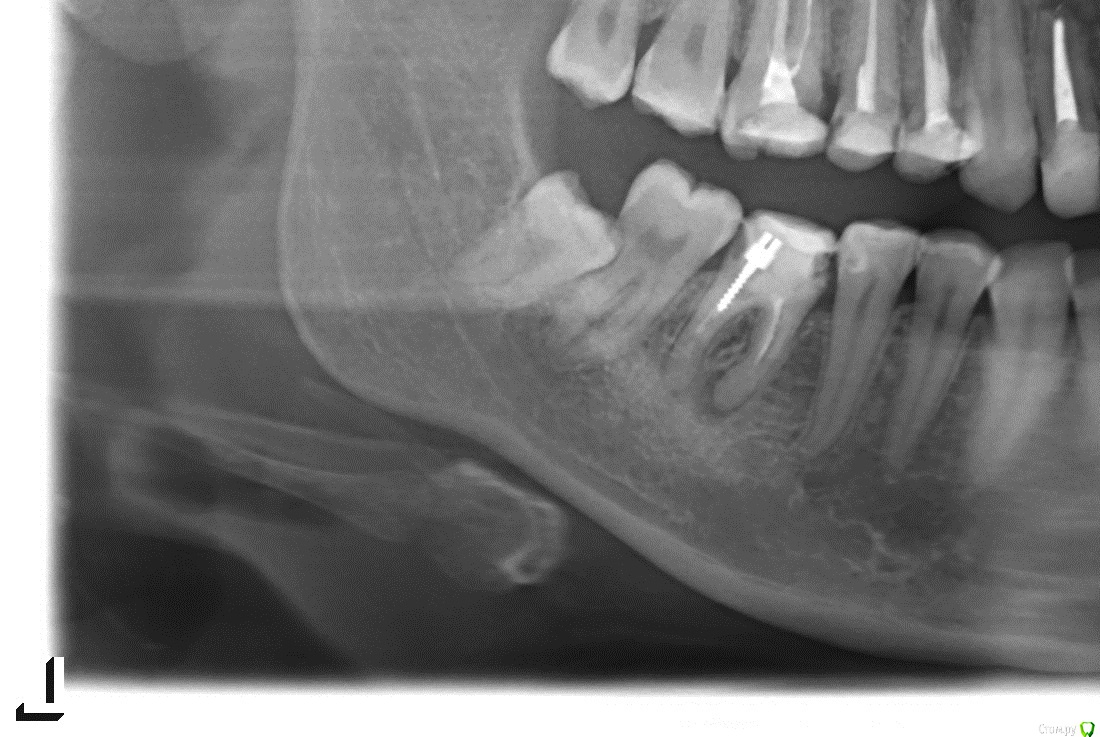

Анна 1986 Опубликовано 5 июня, 2015 Поделиться Опубликовано 5 июня, 2015 Посмотрите пожалуйста по снимку на шестерку, там киста и мнение врачей в моем городе разделилось, кто-то говорит лечить (но дорого и долго), кто-то не маяться ("спасать тут нечего - и каналы плохо залечены и от пломбы ничего не осталось") и удалять и ставить имплант Ваше мнение? Ссылка на комментарий

red_butler Опубликовано 5 июня, 2015 Поделиться Опубликовано 5 июня, 2015 Я бы лечилменя фуркация смущает, уж больно разбита Ссылка на комментарий

Гарриевич Опубликовано 5 июня, 2015 Поделиться Опубликовано 5 июня, 2015 меня фуркация смущает, уж больно разбитаЗуб вообще потрепанный,Но при адекватном лечении думаю выживетЕстественно если в реале все как минимум так же, как на снимке Ссылка на комментарий

red_butler Опубликовано 6 июня, 2015 Поделиться Опубликовано 6 июня, 2015 А зачем восьмерку удалять? для того, что бы не потерять седьмой зуб Ссылка на комментарий